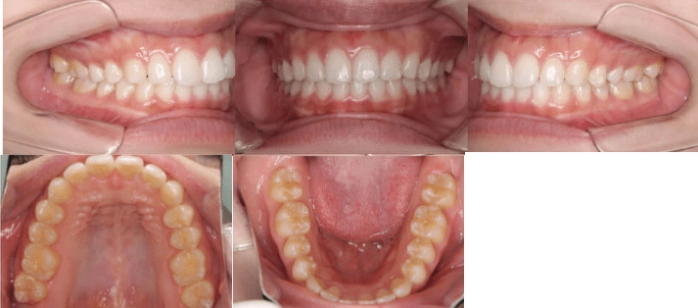

<Before>

<After>

部分矯正

年齢:23歳

治療期間:6ヶ月

主訴:出っ歯

診断:叢生を伴う骨格性I級、非抜歯

治療内容:前歯に隙間があり、捻れてしまっています。マウスピース矯正で治しました。

リスク:矯正治療による歯の移動に伴う痛み、歯根吸収、虫歯

費用:約40万円